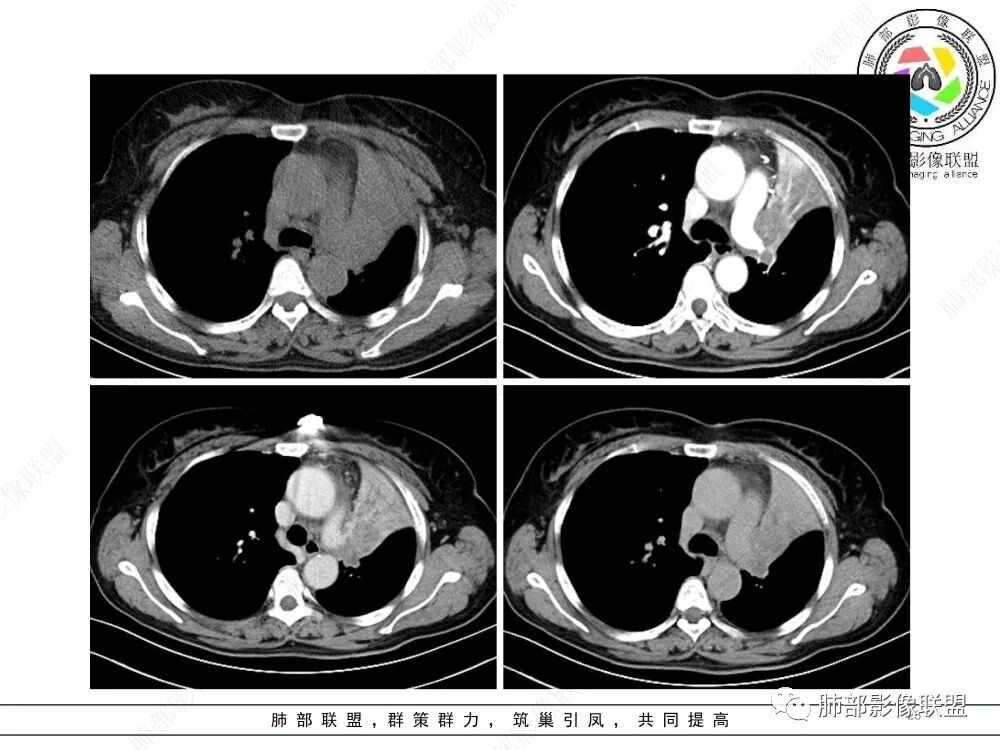

2、影像表现:正常肺背景,左肺上叶支气管腔内占位,上叶支气管截断,远端肺组织不张,强化差异衬托出肺门区结节影或块状影。增强扫描腔内占位轻中度不均匀强化,可见坏死,远端粘液栓,局部肺动脉受压、侵犯,纵膈淋巴结无明显肿大,无胸腔积液。

3、综合分析:老年女性,支气管腔内占位明确,病灶向周围侵犯,诊断恶性肿瘤并肺不张问题不大。需要考虑到的疾病谱有鳞癌、腺样囊性癌、粘液表皮样癌、类癌、小细胞肺癌等。